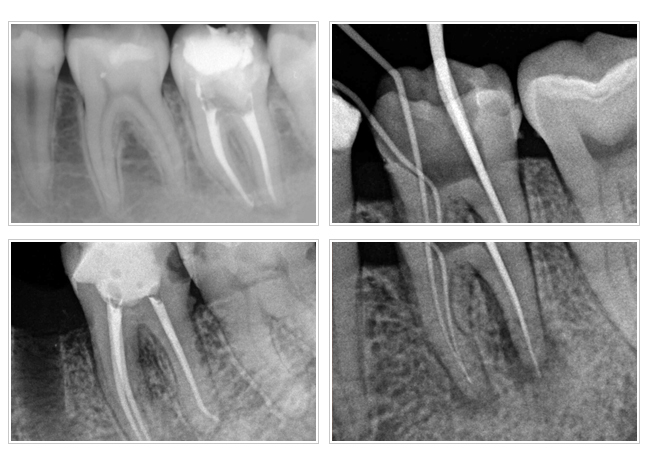

四、複雜根管型態,如:根管分岔、帶狀根管。

五、前次治療發生之意外狀況。

根管治療專科醫師,在接受訓練乃至執業後均以能純熟處理上述困難病例為目標,再加上近年來科技的進步,顯微鏡、超音波器械及鎳鈦合金器械被引進根管治療專科的領域,使得根管治療專科醫師得以藉由顯微鏡的強力照明及最大道25 倍的有效放大,看清楚細微根管的深處角落並加以有效清理感染源,保留更多在過去無法保留的牙齒。因此整合了顯微鏡的專科治療,可以稱為顯微根管專科治療。

顯微根管治療已是美國根管治療的主流,顯微鏡可以把根管放大 到25倍,並有強光照明,改善傳統根管治療無法看到根管內部的盲 點,可以克服大多數的難症,增加治療的成功率。本院專科醫師採用德國蔡司顯微鏡及專為顯微根管治療設計的顯微超音波器械,執行高科技的顯微治療。